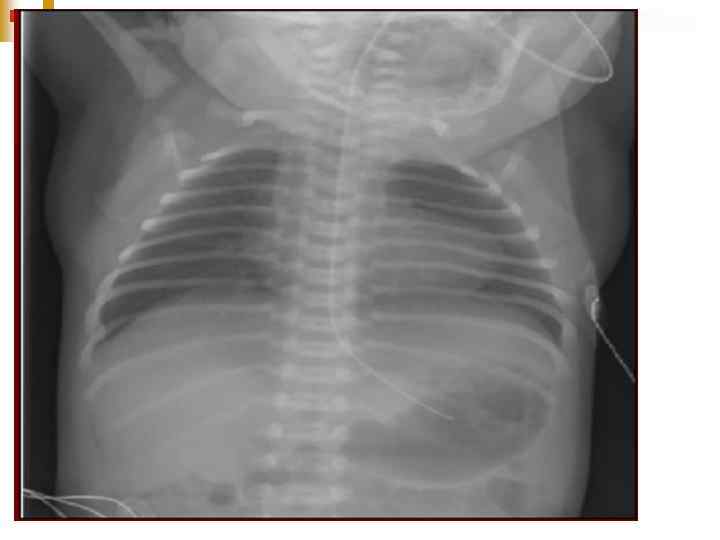

Ventricular septal defect, large left to right shunt